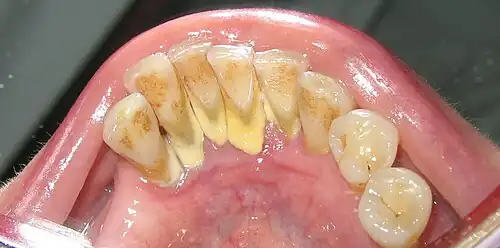

In dentistry, calculus or tartar is a form of hardened dental plaque. It is caused by precipitation of minerals from saliva and gingival crevicular fluid (GCF) in plaque on the teeth. This process of precipitation kills the bacterial cells within dental plaque, but the rough and hardened surface that is formed provides an ideal surface for further plaque formation. This leads to calculus buildup, which compromises the health of the gingiva (gums). Calculus can form both along the gumline, where it is referred to as supragingival ('above the gum'), and within the narrow sulcus that exists between the teeth and the gingiva, where it is referred to as subgingival ('below the gum').

Supragingival calculus formation is most abundant on the buccal (cheek) surfaces of the maxillary (upper jaw) molars and on the lingual (tongue) surfaces of the mandibular (lower jaw) incisors.[18] These areas experience high salivary flow because of their proximity to the parotid and sublingual salivary glands.